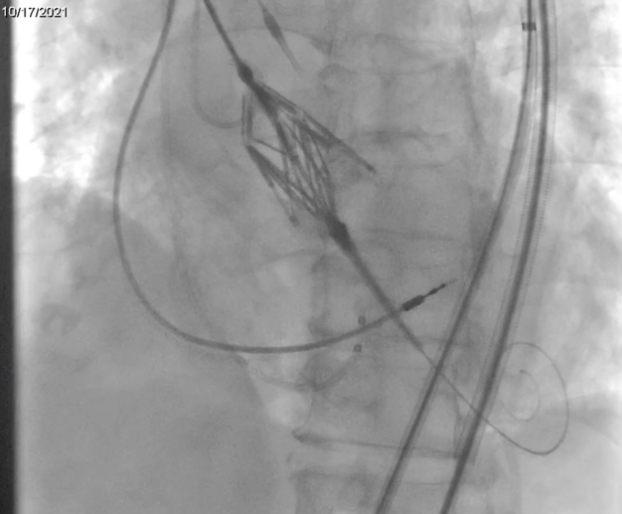

利用Leaflex™ Performer 360°可旋转功能对瓣叶钙化组织进行不同角度压刻修复

在利用Leaflex™ Performer器械从多角度进行自体主瓣修复过程中,患者血流动力学保持稳定,该过程无需在起搏的条件下进行操作,完成修复后主动脉瓣反流未加重。TEE测得患者瓣口峰值流速降低37.4%,峰值压差降低58.9%,平均压差降低56.4%。修复完成后,顺利撤回Leaflex™ Performer器械。患者术后恢复良好,于2021年10月27日出院。